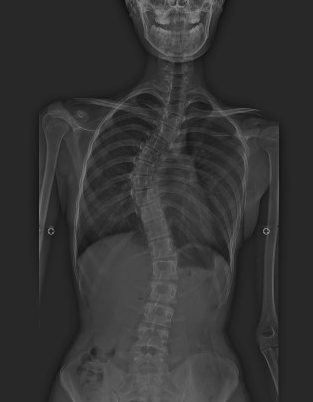

일부 환자는 경미하거나 단 한 가지 증상만이 발생할 수도 있고 일부 환자에게서는 더욱 심각한 합병증이 나타날 수 있습니다. 대부분의 마르팡 환자의 경우 환자 절반이 척추가 S자형으로 휘어지는 척추측만증을 겪습니다.

또한 근력이 정상인에 비해 떨어질 수 있으며, 오목가슴과 새가슴도 생길 수 있습니다.

가슴뼈의 변형과 척추측만증 등은 정형외과적 관리가 필요합니다.

척추측만증일 경우 수술 안정화가 필요할 수 있습니다.